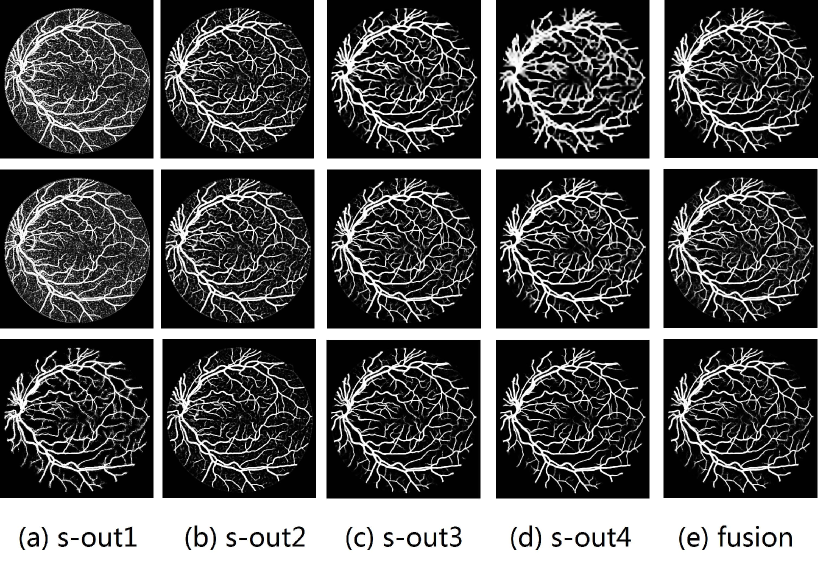

As pointed out in recent works [15, 17], a good semantic segmentation network should learn multi-level features. Further, it should have multiple stages with different receptive fields to learn more inherent features from different scales. FCN, taken as an example, uses skip connections to fuse multiple stages outputs, as well as the HED network, in which a series of side-output layers are added after each stage in VGGNet. The HED network was first proposed for edge detection, and further used for image-level vessel segmentation in recent studies [6, 16], with significant performance. However, our experimental results show that such network architecture is not appropriate for vessel segmentation directly. Figure 1 provides such an illustration. Reasons for this phenomenon are straightforward. On one hand, the side-output of the first layer often contains too many noises. On the other hand, the features produced by the last side-output layer are too coarse due to information loss of pooling operation. Obviously, the inaccurate vessel map of side-output1 and side-output4 should have negative impacts on the final segmentation result.

2.2 Bottom-top short connections

With the deepening of DSN network, the receptive field of each side-output layer gets larger, which makes the corresponding vessel map much blurrier as observed from the first row in Figure 1, especially for side-output4. These observations inspired us to pass low level fine semantic information to high levels to alleviate the blurring situation.

Bottom-top short connections aim to refine high-level segmentation results. However, we can observe from the first two rows in Figure 1 that the vessel map generated by the first side-output layer contains too many noises while the map generated by the last side-output could capture the main vessel structure. Therefore, we propose delivering high-level structural information to the first side-output layer to reduce its noises. We implemented this kind of information delivery by a top-bottom short connection from conv4 to feat_conv1, which can been seen in Figure 4. We first convolved the last convolution of conv4 using 1 convolution kernels with size 33. Then the obtained feature map are up-sampled 8 to get feat_4_1. The information (feat_4_1) passed from conv4 are concatenated with feat_conv1 to form feat_conv1_fuse (see Figure 5). At last, one hand hand, we perform a 11 convolution operation on feat_conv1_fuse to get the information (feat_1_2) delivered to feat_conv2. On the other hand, we performed convolution operation with a kernel size of 11 and sigmoid transformation for feat_conv1_fuse sequentially to obtain the segmentation result (side 1). At last, side 1 is compared with the ground truth to get the loss of the first side-output layer.

In addition, we can observe from Figure 1 that the side-output1 and side-output4 of the BTS-DSN were more accurate compared with those of the DSN.